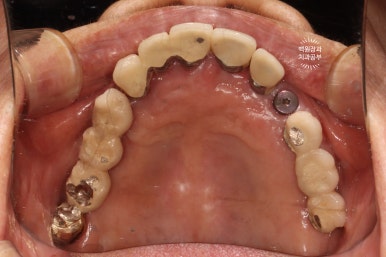

처음 오셨을 때 정면 사진입니다.

잘 보시면, 아까 보였던 치과용 파노라마 사진대로 뿌리만 남은 두 개의 치아를 찾아보실 수 있으실거에요. ㅎㅎ

좌측은 위턱 사진, 오른쪽은 아래턱 구강내 사진입니다.

아주 어렵지 않게 두 치아가 부러져 있다는 것을 확인할 수 있죠.

위턱의 씹는면을 보시면, 스트라우만 임플란트로 아주 깔끔히 치료된 것을 보실 수 있습니다.

옛날에 치료받았던 스트라우만 임플란트는 이제 오래되어... 조금 깨지도 닳은 것은 보이나, 사실 기능하는데는 문제가 없었어요. 20년이 넘었음에도 이렇게 훌륭한 임상결과를 보이는 스트라우만 임플란트. 정말 최고임을 직접 보여주고 있었습니다. 진짜 올타임 넘버원 임플란트입니다.